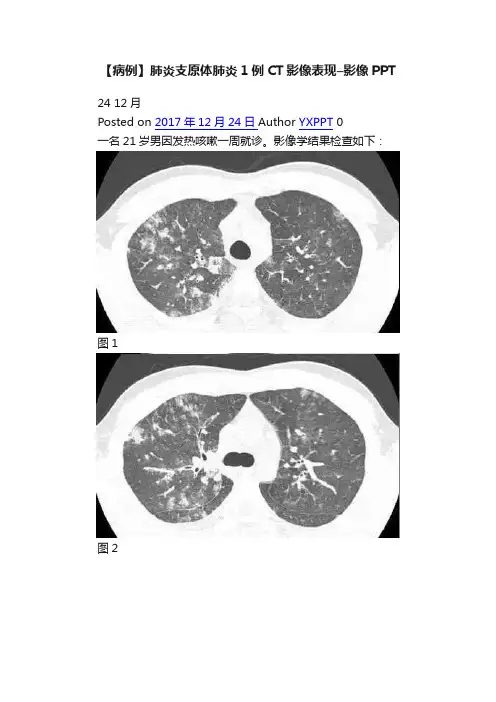

一名21岁男因发热咳嗽一周就诊。

影像学结果检查如下:

胸部CT(图1-3)显示,支气管壁增厚,小叶中央型结节,磨玻璃影或小叶实变,轴向间质和小叶间隔增厚,以及双侧少量胸腔积液。

最终诊断:肺炎支原体肺炎

CT 上,最常见的是支气管壁增厚(81%),其次是小叶中央型结节(78%),磨玻璃影(78%)和小叶实变(61%)。

轴向间质及小叶间隔增厚常见。